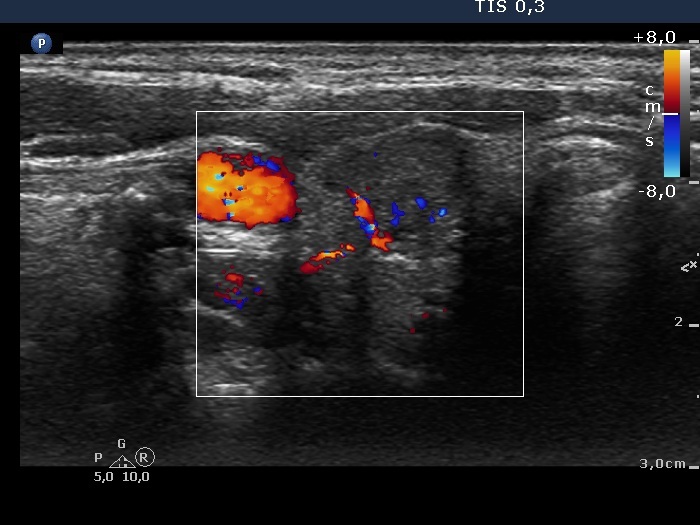

Teamwork - case 894 (ultrasonographic picture 7)

Right lobe, transverse scan, color Doppler mode, enlarged view. The nodule presents signs of intranodular vascularity. There is a large vessel at the edge of the lesion.